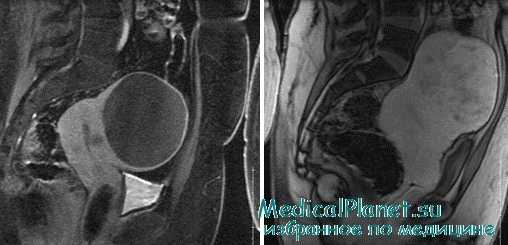

Перед проведением эмболизации маточных артерий женщину тщательно обследуют. Гинеколог осматривает, консультирует пациентку и изучает ее историю болезни, оценивает общее состояние, выясняет, есть ли у нее другие проблемы со здоровьем. Обязательно проведение УЗИ (в некоторых случаях — МРТ). Всё это нужно для того, чтобы оценить, показана ли ЭМА как метод лечения миомы матки в данном случае, является ли оптимальным выбором.

Это вмешательство, которое проводится в рентгенологической операционной сосудистым хирургом под местной анестезией. Через пункцию и катетеризацию бедренной артерии проводят традиционную катетерную серийную тазовую ангиографию, а затем селективную катетеризацию и артериографию маточных артерий. Затем через этот катетер выполняют эмболизацию маточной артерии. Для этого используют металлические спирали, частицы ПВА, гидрогель, акриловые микросферы. По окончанию процедуры выполняют контрольную артериографию, катетер удаляется из артерии и осуществляется гемостаз. Время операции от 50 мин до 1,5 часов.

Во время эмболизации происходит прекращение тока крови в миоме и менее значительно в стенке матки, что приводит к развитию ишемического инфаркта опухоли с последующей ее дегенерации. Редко некроз узла может приводить к развитию клиники «острого живота» и перитонита, что требует экстренного оперативного вмешательства. Суть метода – это необратимая эмболизация сосуда (частицами размером 355-500 мкм), питающего миоматозный узел и тело матки (при остановке кровотечения).